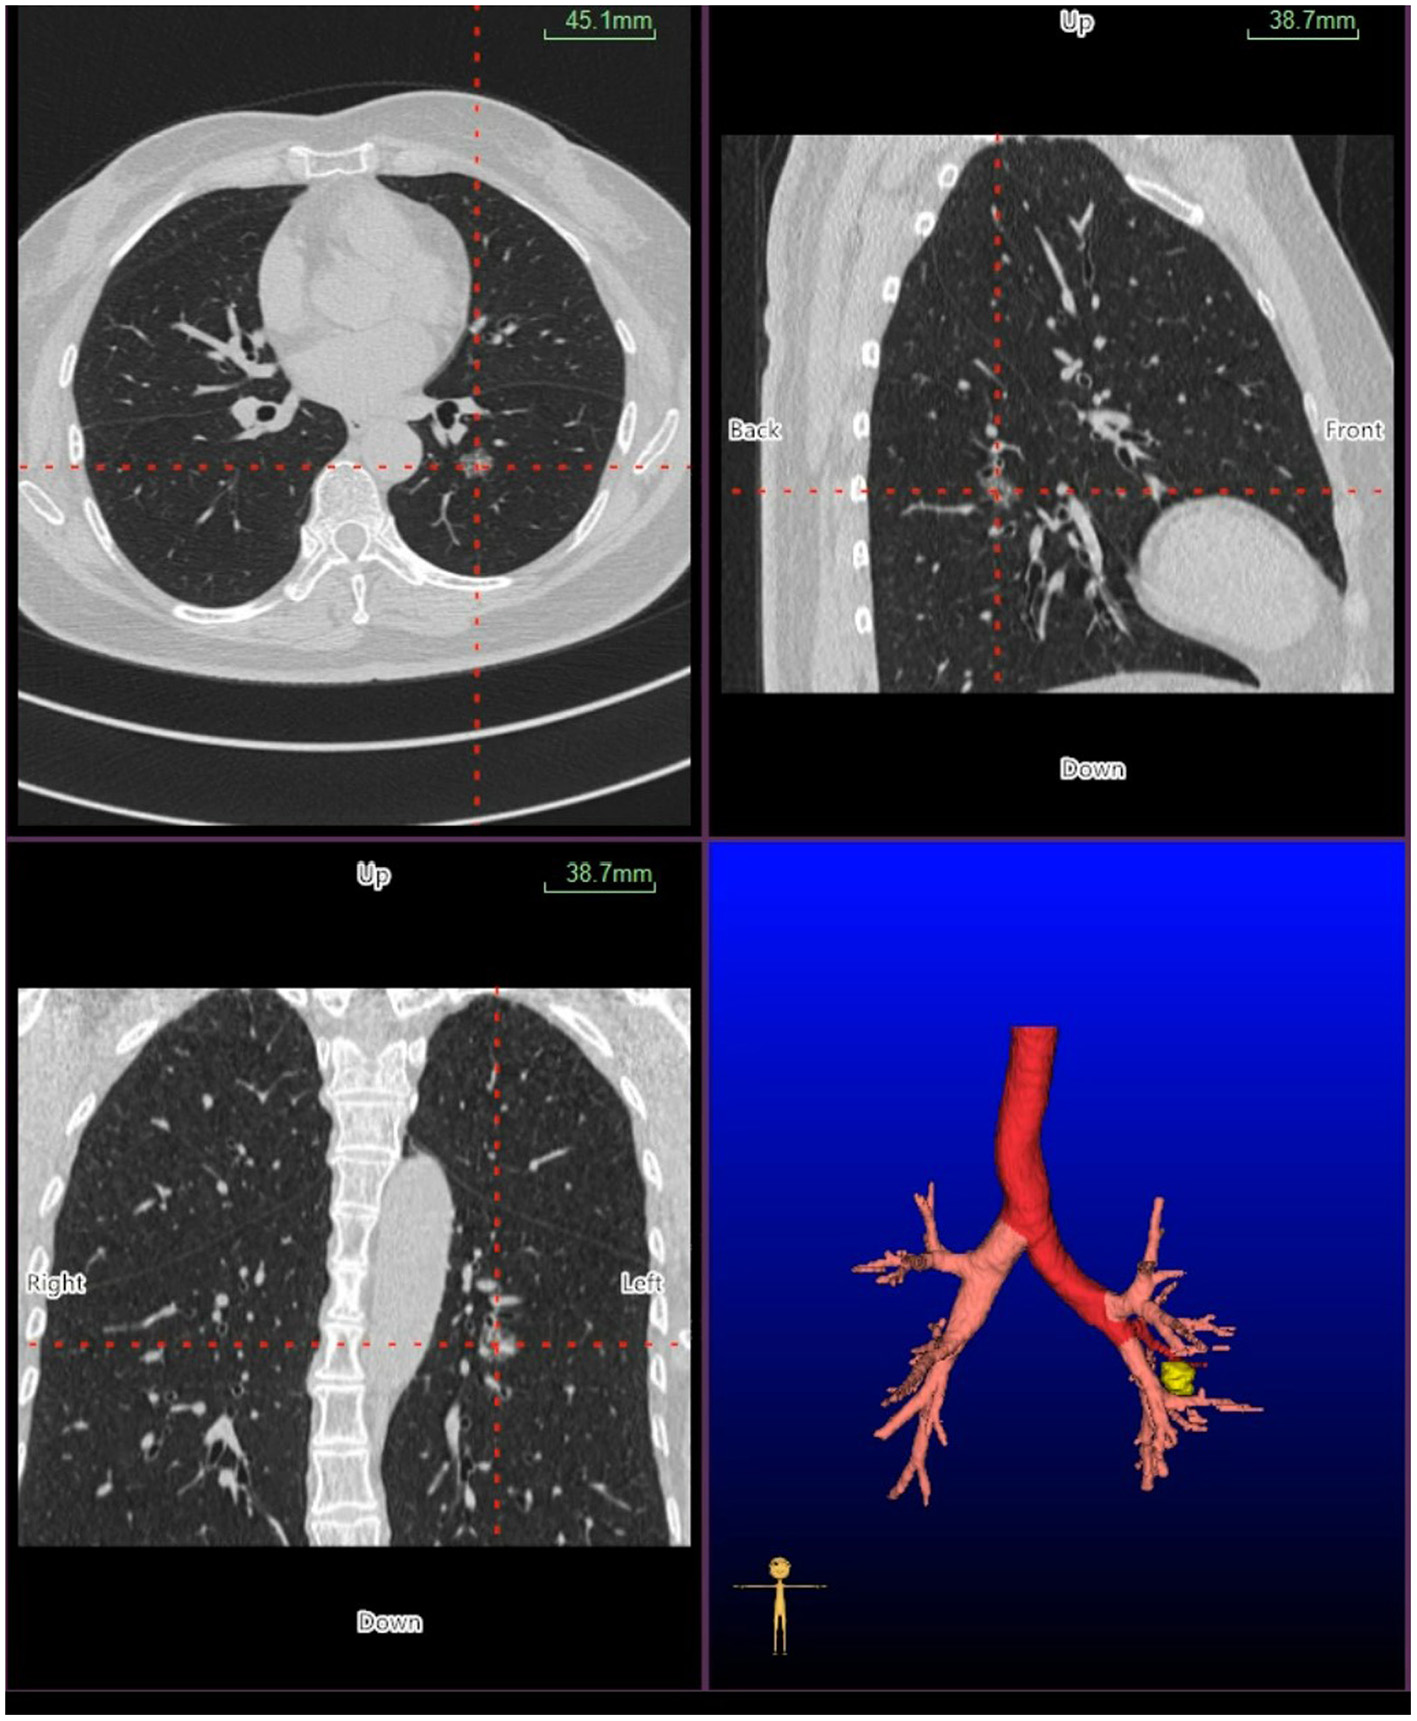

Virtual bronchoscopic navigation is a navigational technique that utilizes data of helical CT to construct three-dimensional virtual images of the bronchial route to guide the bronchoscope to the target lesion (Figure 1). Bf-NAVI® (Cybernet System Inc., Tokyo, Japan) was the first VBN system that was introduced in Japan in 2008, LungPoint® (Broncus Medical Inc., Mountain View, CA, USA) was launched in 2009 in the USA and is now widely used in the USA and European countries (10). DirectPath® (Cybernet System Inc.), which has replaced Bf-NAVI, is used in China by most centers. There are mainly 3 phases of virtual bronchoscopic navigation: planning, guidance, and biopsy. (i) Planning phase: In the planning phase, data from multi-detector chest CT of patients are imported to the computer via VBN software (Figure 2), which automatically creates the virtual bronchoscopic pathway to the target lesion (Figure 3). To obtain high-quality virtual bronchoscopic (VB) images, continuous volume CT data is required. Planning is a pre-bronchoscopy process that is usually done on the same day or days before the intended biopsy. (ii) Guidance phase: The virtual images acquired during the planning phase are used to advance the bronchoscope manually to the target lesion, and the position of the bronchoscope tip can be displayed on the CT images corresponding to the bronchial tree. (iii) Biopsy phase: The choice of procedure to biopsy lesion depends on patient selection and target disease. PPLs can be sampled with flexible bronchoscopy, ultrathin bronchoscopy, and radial endobronchial ultrasound probes (RP-EBUS).

Figure 2

Planning phase- multi-planar views of the target peripheral pulmonary lesion (axial, sagittal, coronal, and 3D map).